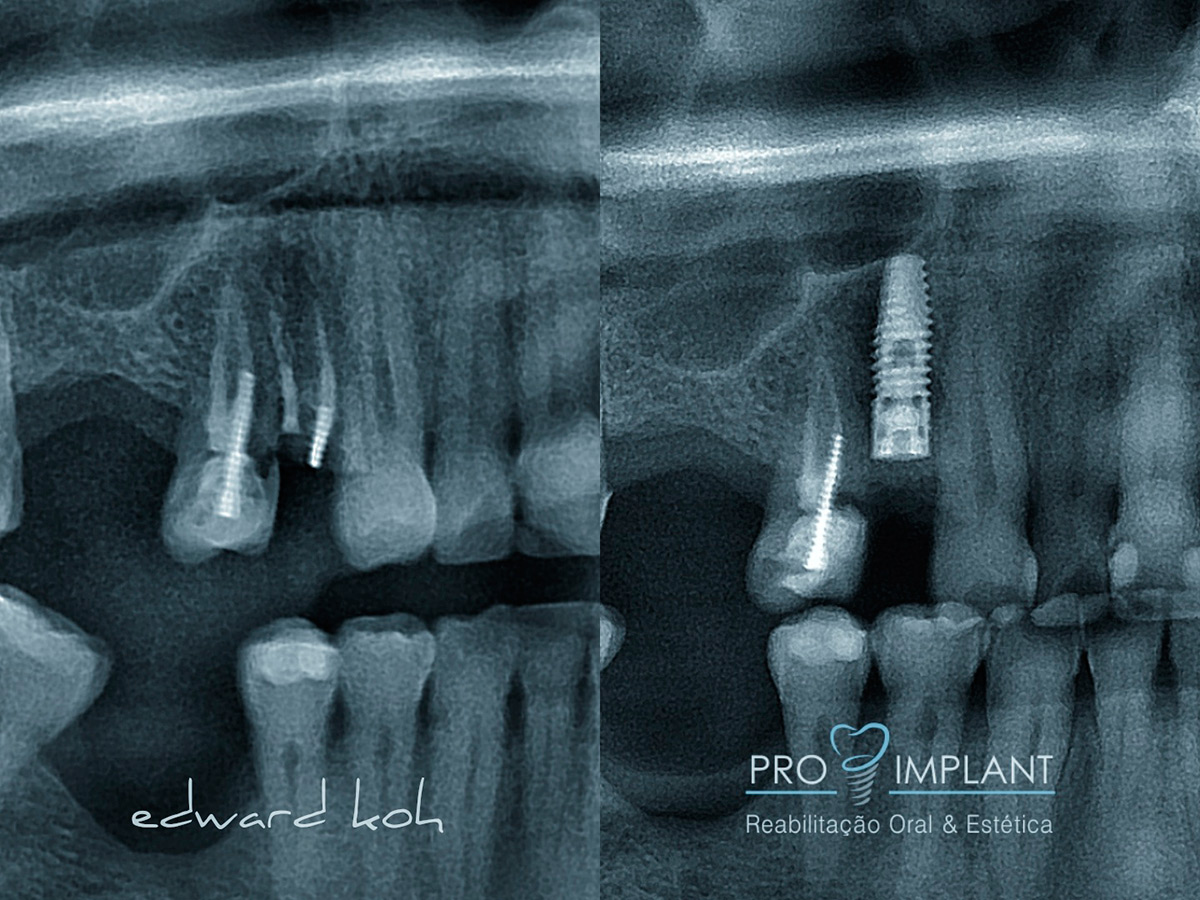

A perda de dentes pode levar a problemas estéticos, de oclusão (mordida) e perda óssea. Portanto é fundamental uma rápida reposição do elemento perdido. Os Implantes Dentários são parafusos de titânio que substituem a raiz dos dentes perdidos. O implante dental serve de apoio para a prótese (coroa) que deve ser semelhante aos dentes: naturais em estética e função. Os Implantes Dentários podem ser indicados para repor a perda de todos os dentes, de alguns ou de apenas um dente.

Em alguns casos, os implantes podem ser utilizados para suportar a prótese logo após sua instalação, num procedimento conhecido como carga imediata, por meio do qual podemos fazer reabilitações totais ou parciais.

O Implante Dentário inibe a atrofia do osso após a perda de um dente; é fixo e não há necessidade de comprometer os dentes naturais adjacentes.